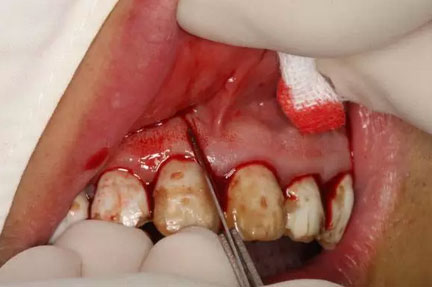

圖9.切口的交界處翻瓣,注意翻全厚瓣。

圖10.翻開(kāi)粘膜瓣發(fā)現(xiàn)有唇側(cè)部分骨壁不規(guī)則缺損。